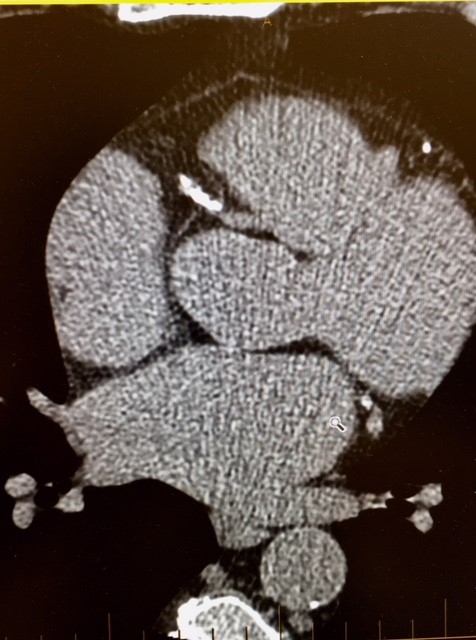

Figures 1-8: Examples of CAC Images

Figure 2: Right Coronary Artery without calcification and calcium score of zero is free of calcified plaque.

Figure 3: Right Coronary Artery calcification demonstrated in patient with total CAC score over 1000.  Note that calcification involves arterial wall seen in cross section here.

Figure 4: Left Circumflex Artery calcification demonstrated bottom right with score for this artery of 90.  Note the normal non-calcified Right Coronary Artery seen at top left.

Figure 5: Left Anterior Descending Artery calcification demonstrated in a patient with mild coronary artery disease with a CAC score of 85.